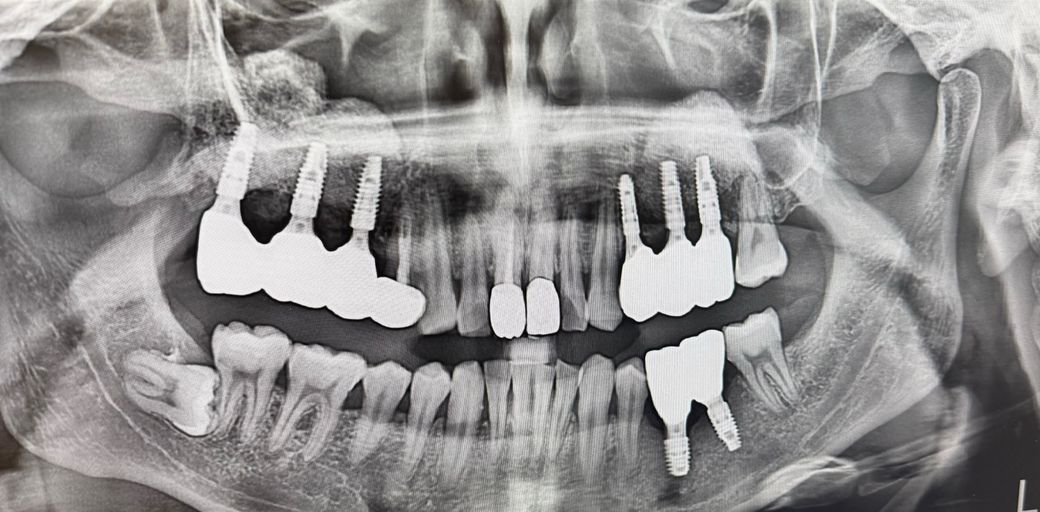

질문으로는 파노라마 사진에서 왼쪽의 상악 보철물의 세번째 잇몸입니다

• 3번 째 사진

엑스레이상으로나 실물 사진으로나 크게 문제가 있어보이는 상태는 아닌 것으로 보입니다.